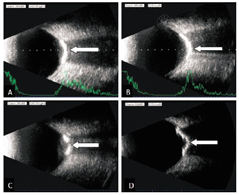

既往5年前头部受过拳击伤,否认全身疾病史及家族史。眼科检查:视力右0.3,矫正无提高,左0.07,矫正无提高;眼压:右19.0 mmHg,左17.8 mmHg。双眼前节正常,散瞳见双眼低,如图1A、图1B。眼部B超检查如图2A、图2B。眼眶CT扫描:双侧眼球后壁见对称性高密度弧形钙化影(箭头所指),较长者直径0.7 cm,最高CT值468 Hu(图3A)。荧光素眼底血管造影(fundus fluorescein angiography,FFA)图4。结合眼底相、B超、眼眶CT及FFA检查,诊断:双眼脉络膜骨瘤。

病例2:患者女,48岁,自述右眼视物不清7年余,左眼10天余,于2016年5月26日来我院就诊。既往8年前头部受过雷击伤,否认全身疾病史及家族史。眼科检查:视力右0.15,-1.00 DC×15→0.25,左数指/30 cm,矫正无提高。双眼前节正常,散瞳见双眼底如图1C、图1D。眼部B超检查如图2C、图2D。眼眶CT扫描:双侧眼环后份及周围局部眼球可见条状高密度钙化影(箭头所指),最高CT值572 Hu(图3B)。双眼FFA如图5,诊断:双眼脉络膜骨瘤。

B超的典型声像特征为近乳头附近可见条形强回声斑,其后方声影明显,降低增益值此强回声斑仍存在,而球壁等正常组织的回声减弱甚至消失[7],但肿瘤回声仍存在。脉络膜骨瘤特征性的CT表现为眼球后极部眼环上呈现弧形或半环状光滑锐利的致密影[8],脉络膜骨瘤行FFA检查早期即有强荧光点出现,强荧光代表肿瘤内异常脉络膜血管,晚期时不规则弥漫斑点状强荧光持续存在[9]。本文2例患者改变与上述相符合。